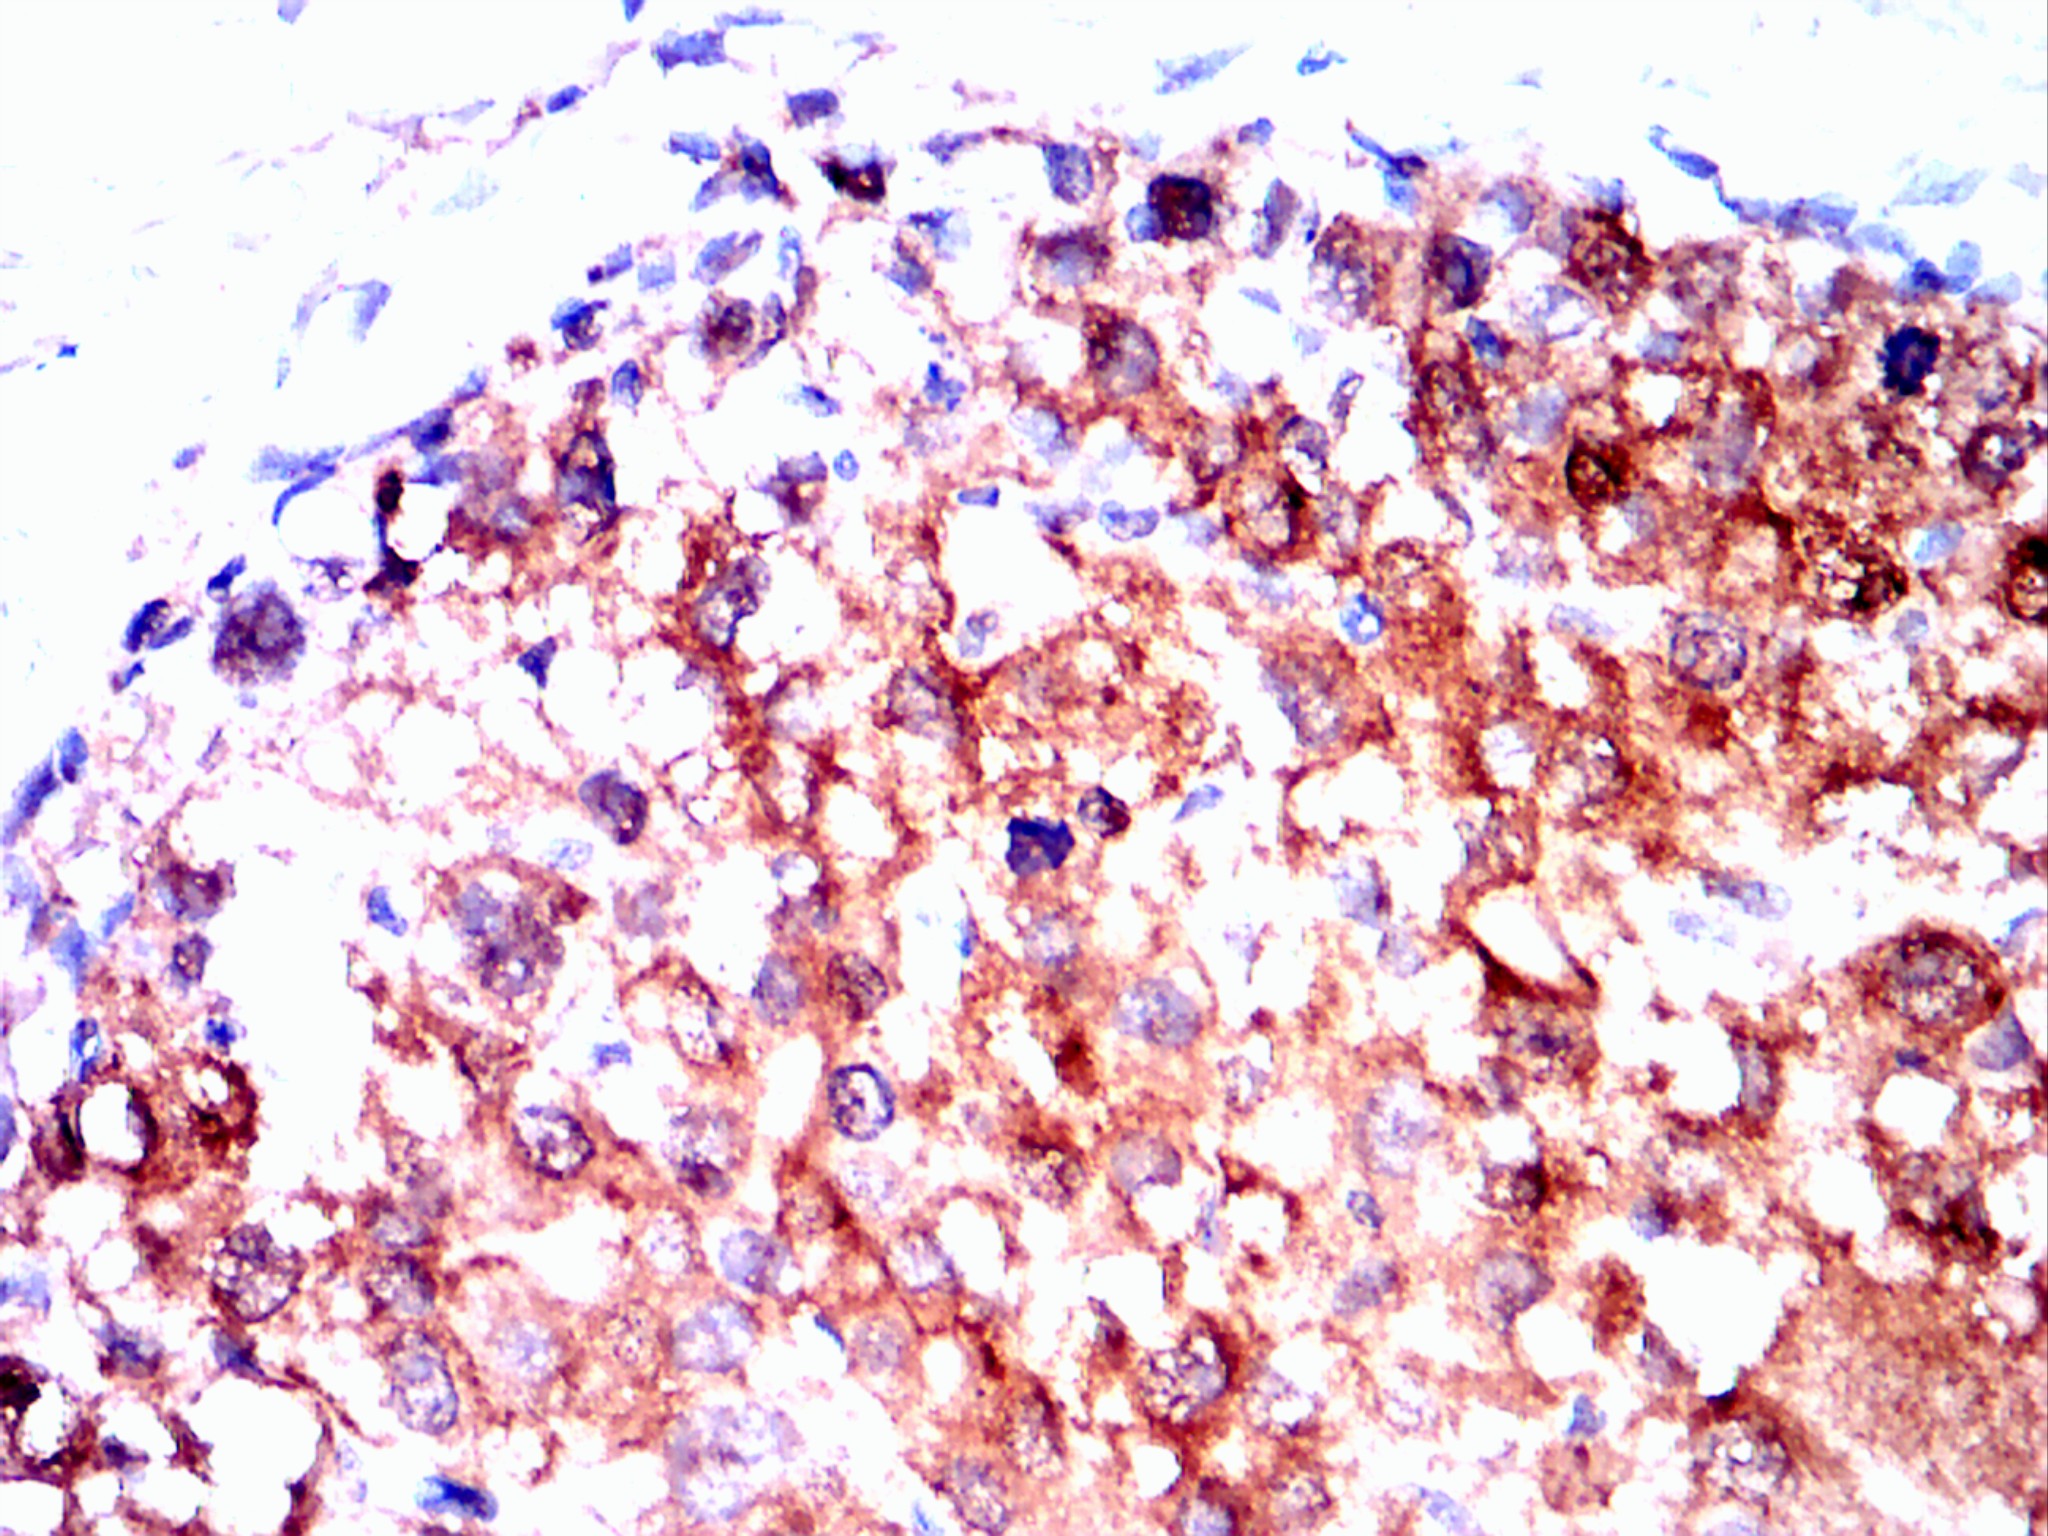

Immunohistochemical analysis of paraffin-embedded liver cancer tissues using Visfatin(PBEF) mouse mAb with DAB staining.